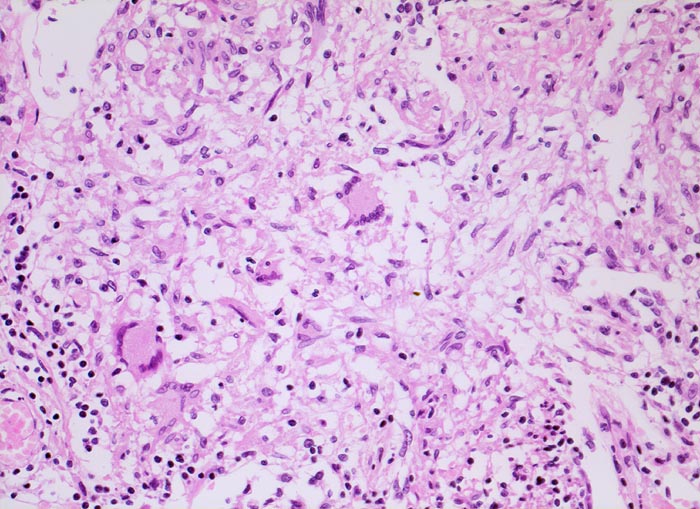

PathoPic – image database / PathoPic ID 4834 - Tuberkulosegranulom

Tuberkulosegranulom

Schlanke spindelige Epitheloidzellen und einzelne Riesenzellen vom Langhanstyp mit peripher hufeisenförmig angeordneten Kernen. Am Rand kleine Lymphozyten.

Die Epitheloidzellen in einem Tuberkulosegranulom sind in der Regel schlank. Die Epitheloidzelle des Sarkoidosegranuloms haben mehr Zytoplasma und plumpere Kerne. Verkäsende Nekrosen kommen allerdings auch bei Sarkoidosegranulomen vor. Vrgl. PathoPic ID 4042